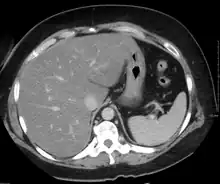

On X-ray computed tomography (CT), the increased fat component will decrease the density of the liver tissue, making the image less bright. Typically the density of the spleen and liver are roughly equivalent. In steatosis, there is a difference between the density and brightness of the two organs, with the liver appearing darker.[12] On ultrasound, fat is more echogenic (capable of reflecting sound waves). The combination of liver steatosis being dark on CT and bright on ultrasound is sometimes known as the flip flop sign.